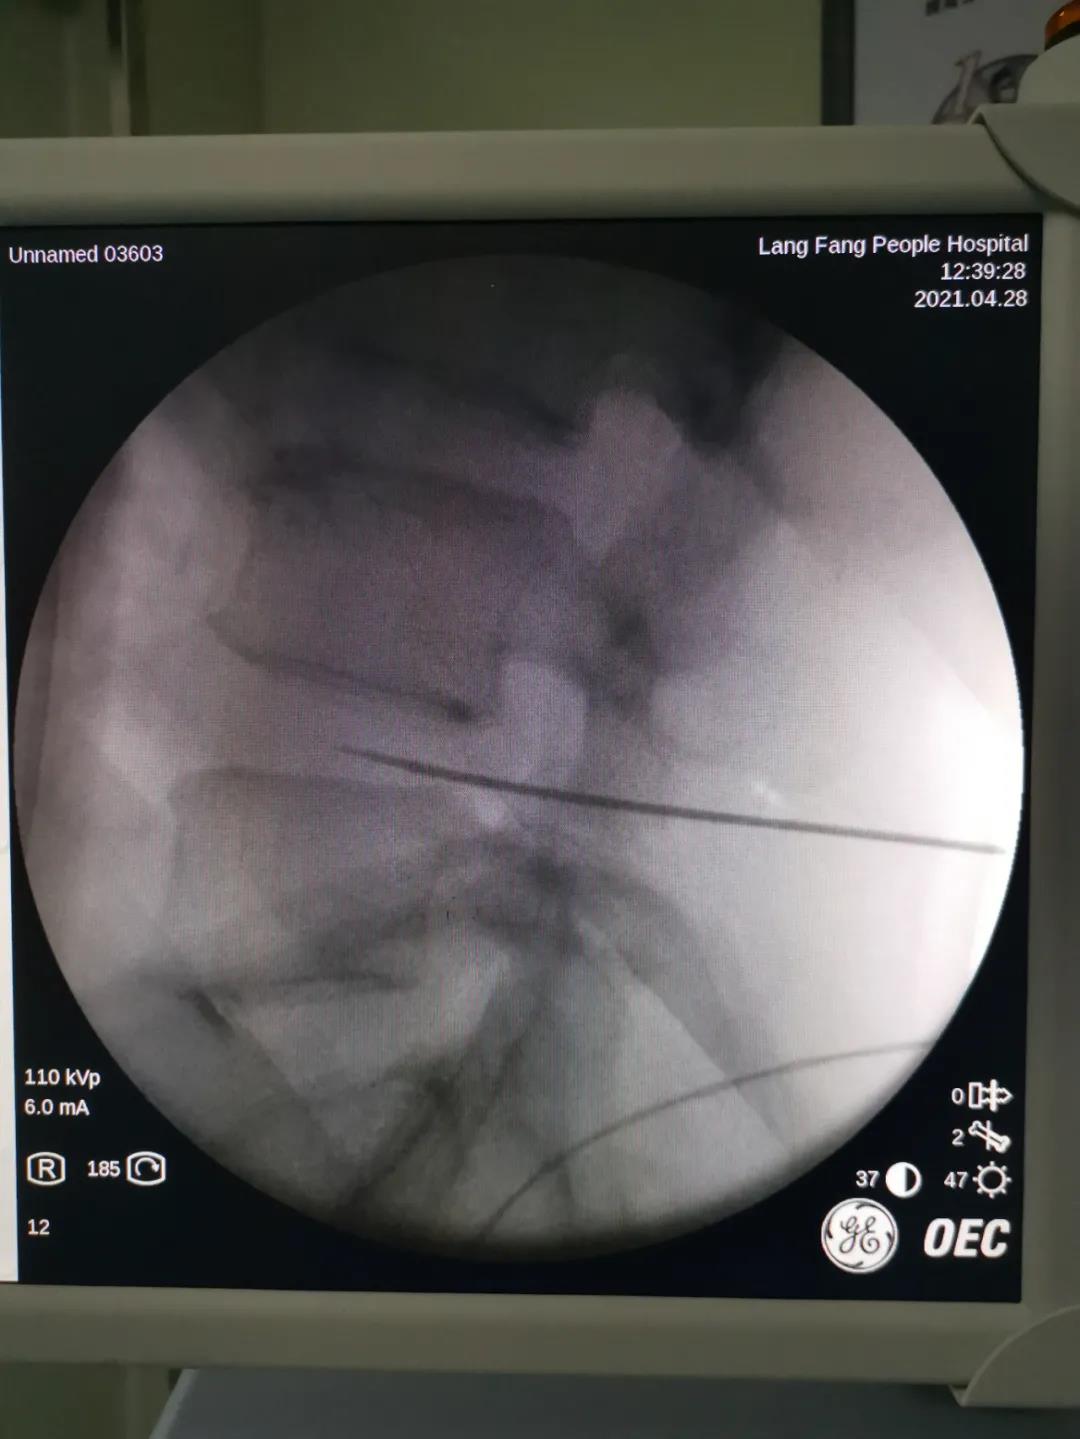

在C臂X光机下准确定位,直接作用在病变的髓核上,数据精确到1mm以下,角度误差小于1度,使治疗更精确。